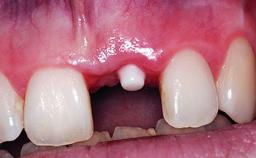

A 32-year-old female Caucasian patient with a compromised maxillary right central incisor was referred to us by a general dentist. Her chief complaints were discomfort and mobility of tooth 11 with unsatisfactory esthetics due to discoloration. The patient reported a previous trauma, some years earlier, as the origin of pathology on the afflicted tooth. Anamnesis was negative for any other dental or periodontal pathology in the remaining dentition. The patient did not take any medication and reported to be a light smoker (5–10 cigs/day). She had high esthetic expectations of her treatment. The extraoral examination revealed a high smile line with full exposure of her maxillary teeth and surrounding soft tissue in the area between the second premolars.

Placement Protocol Early or late implant placement

Loading Protocol Conventional or early

Interim Prosthesis during Healing Fixed Fixed